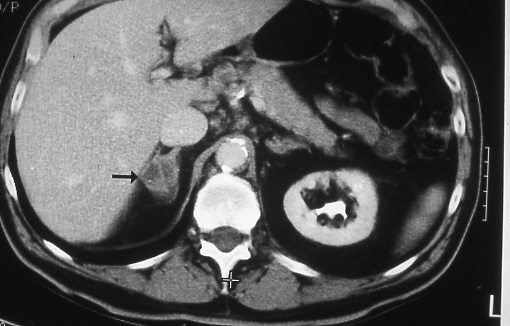

Fig.

30: M1 disease.

A computed tomographic

scan of the abdomen shows

metastatic lung cancer

to the right adrenal

gland. The gland is enlarged

(arrow) and shows areas

of decreased attenuation

in keeping with necrosis. |